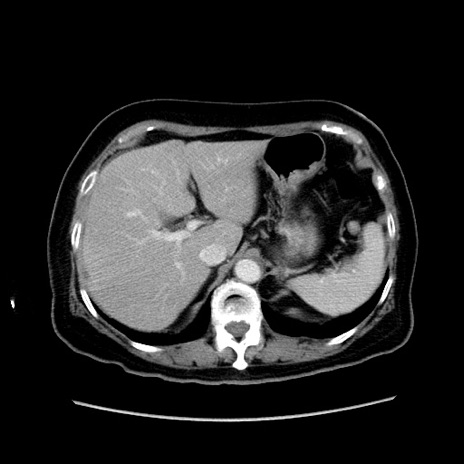

症例19(横断像)

【症例】80歳代女性

【主訴】下腹部痛

【現病歴】約8時間前より下腹部痛の出現あり、救急外来受診。

【既往歴】両側付属器切除

【身体所見】意識清明、下腹部正中に手術痕あり、その部位に一致して圧痛と反跳痛あり。腸蠕動音は亢進。

【データ】WBC 9300、CRP 0.15